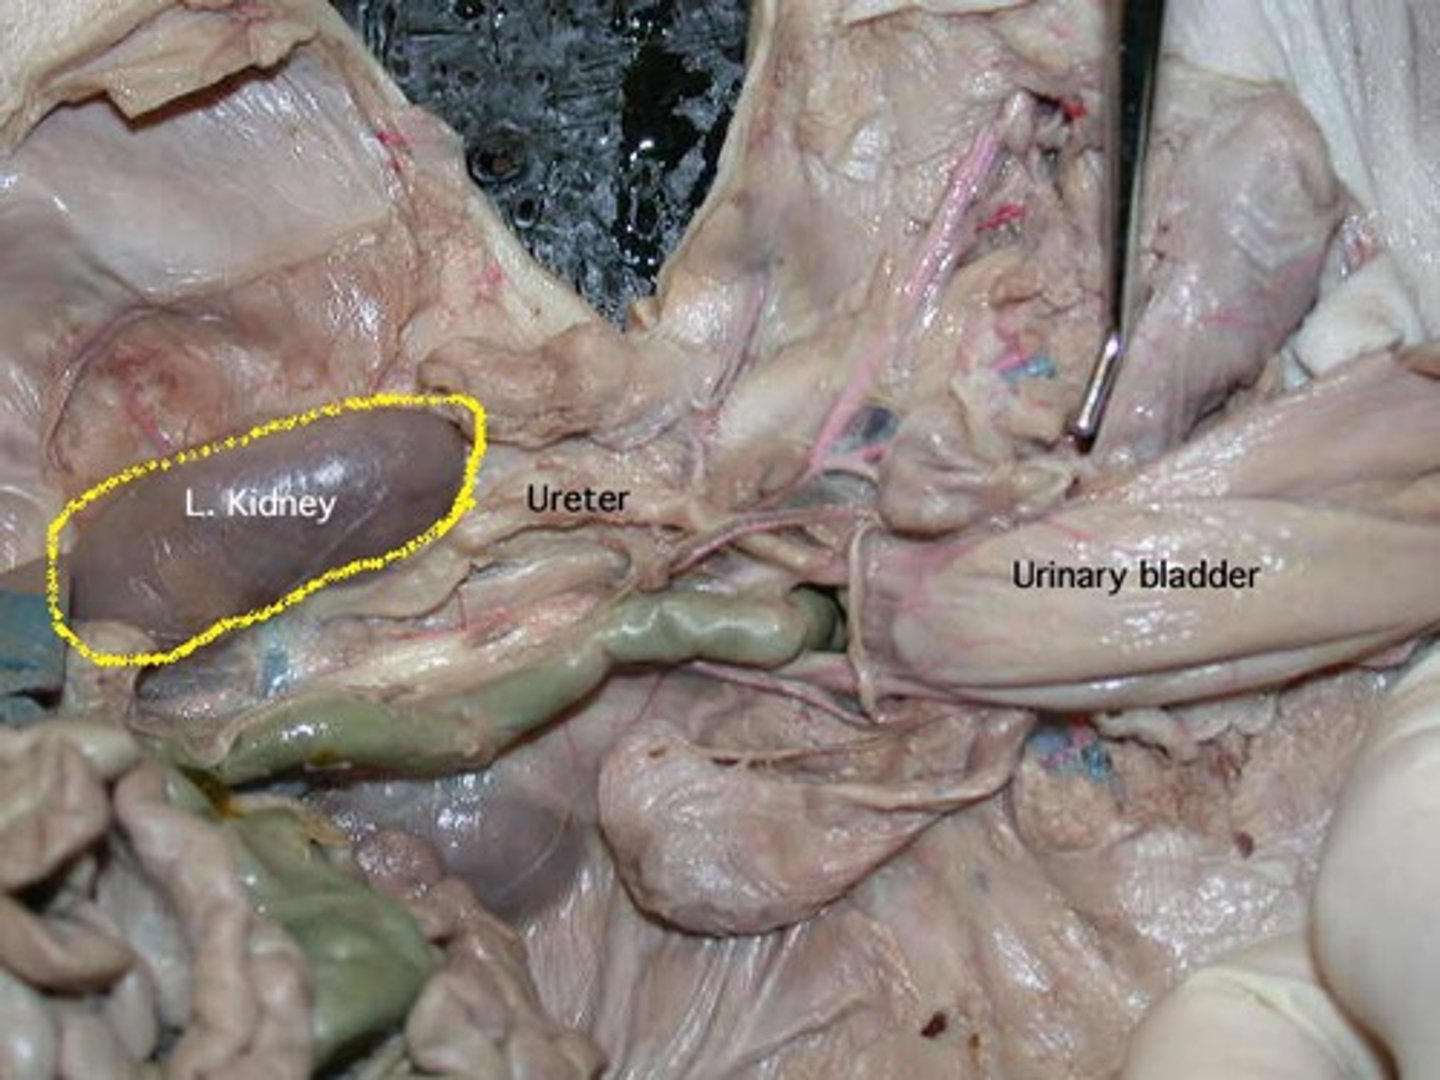

Kidneys - filter, removes waste

Urethra - removal of urine

Allantoic Bladder